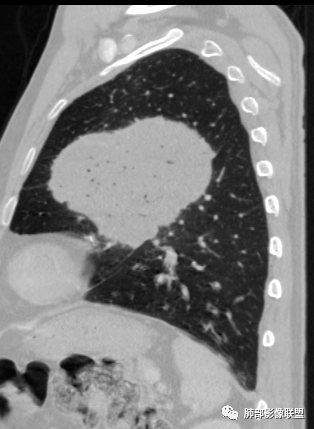

左肺上叶大肿块,膨胀性生长,边界清,密度较低,见部分坏死区,强化弱,肿块见支气管充气V扩张征,分布僵直,枯树枝特点,另一个重要特点血管造影征,淋巴瘤,肿块长轴与胸膜平行,与隐球菌鉴别,隐球荚膜抗原检查,明确诊断经皮肺穿刺。另胸膜钙化(问诊既往有无患胸膜炎病史)。

老年男性,糖尿病病史,消瘦、乏力三个月,影像表现左肺上叶胸膜下团块,有一定张力,内部疏松,可见支气管影及坏死区,增强病灶边缘环形强化,内部未见强化,考虑炎性肉芽肿病变,隐球?奴卡?放线菌?鉴别淋巴瘤。

左肺上叶胸膜下肿块,宽基底与胸膜相连,跨叶裂,边缘清晰膨隆,其内支气管充气,部分扩张、僵直,无明显强化,血管造影征,考虑淋巴瘤,鉴别腺癌

左肺胸膜下巨大占位,跨叶裂,宽基底与胸膜相连,胸膜钙化,平扫密度较低,强化不明显,可见内部血管显影,支气管充气征和扩张,考虑为恶性,倾向于淋巴瘤

我要修正一下观点了:仔细看了视频,肿块占位效应明显,对周围血管,支气管有推挤,增强后强化不明显,NSE增高,半年体重下降25公斤,虽然有内部支气管扩张,血管漂浮,边界清楚支持淋巴瘤,但强化太低,膨隆,占位推挤太明显(淋巴瘤一般没有这么明显的占位效应),胸膜关系有载桩,恶病质明显(乏力,半年体重下降了25公斤),NSE也明显增高,就不支持淋巴瘤了。还是考虑外朝内的恶性肿瘤,间质来源的肉瘤伴有神经内分泌分化或者大神泌。

不支持淋巴瘤的有四点:1、对周围血管支气管推挤明显。2、胸膜有栽桩,3、强化太弱(淋巴瘤一般还是中度以上甚至高度强化多见),4、NSE升高明显,体重下降太明显。

大肿块,边缘光滑,深分叶

近端支气管堵塞、推移为主

部分类似于脐凹征

内部支气管扩张

肺动脉推移为主,边缘部分进入

大肿块、表面光滑但深分叶,肺门侧支气管堵塞

1)部位:周围型或中央型软组织肿块,以周围型为多见,且肿瘤多位于肺上叶。如本例:该肿瘤位于左肺上叶。

2)大小及形态:由于本病恶性程度高,早期症状不明显,发现时肿块均较大。如本例病变巨大。

3)肿块边界和边缘:多较清楚,呈圆形、类圆形,且由于肿块生长速度不均匀,可见分叶,毛刺少见。有报道肿块周围毛玻璃影是多形性癌特征表现。

4)密度:肿块平扫为软组织密度,由于体积较大,内部常见大片状坏死,可出现不规则厚壁空洞或坏死内多发无壁小空洞,坏死多不均匀:坏死灶内可见如柳絮样的斑片样强化灶,坏死边缘与非坏死区分界不清本例坏死较明显,密度不均匀。

5)肿瘤强化方式:肺部恶性肿瘤强化程度与其血供丰富程度相关,血供丰富多强化明显,反之则较差。由于PSC 周边实性部分富血供及内部黏液变性、坏死,增强后肿块多数呈轻-中度边缘环形强化或不均匀小斑片状强化。国外学者对照病理发现肿瘤细胞或胶原组织增强扫描时强化,无强化的低密度区代表了黏液样变性区和出血坏死区。